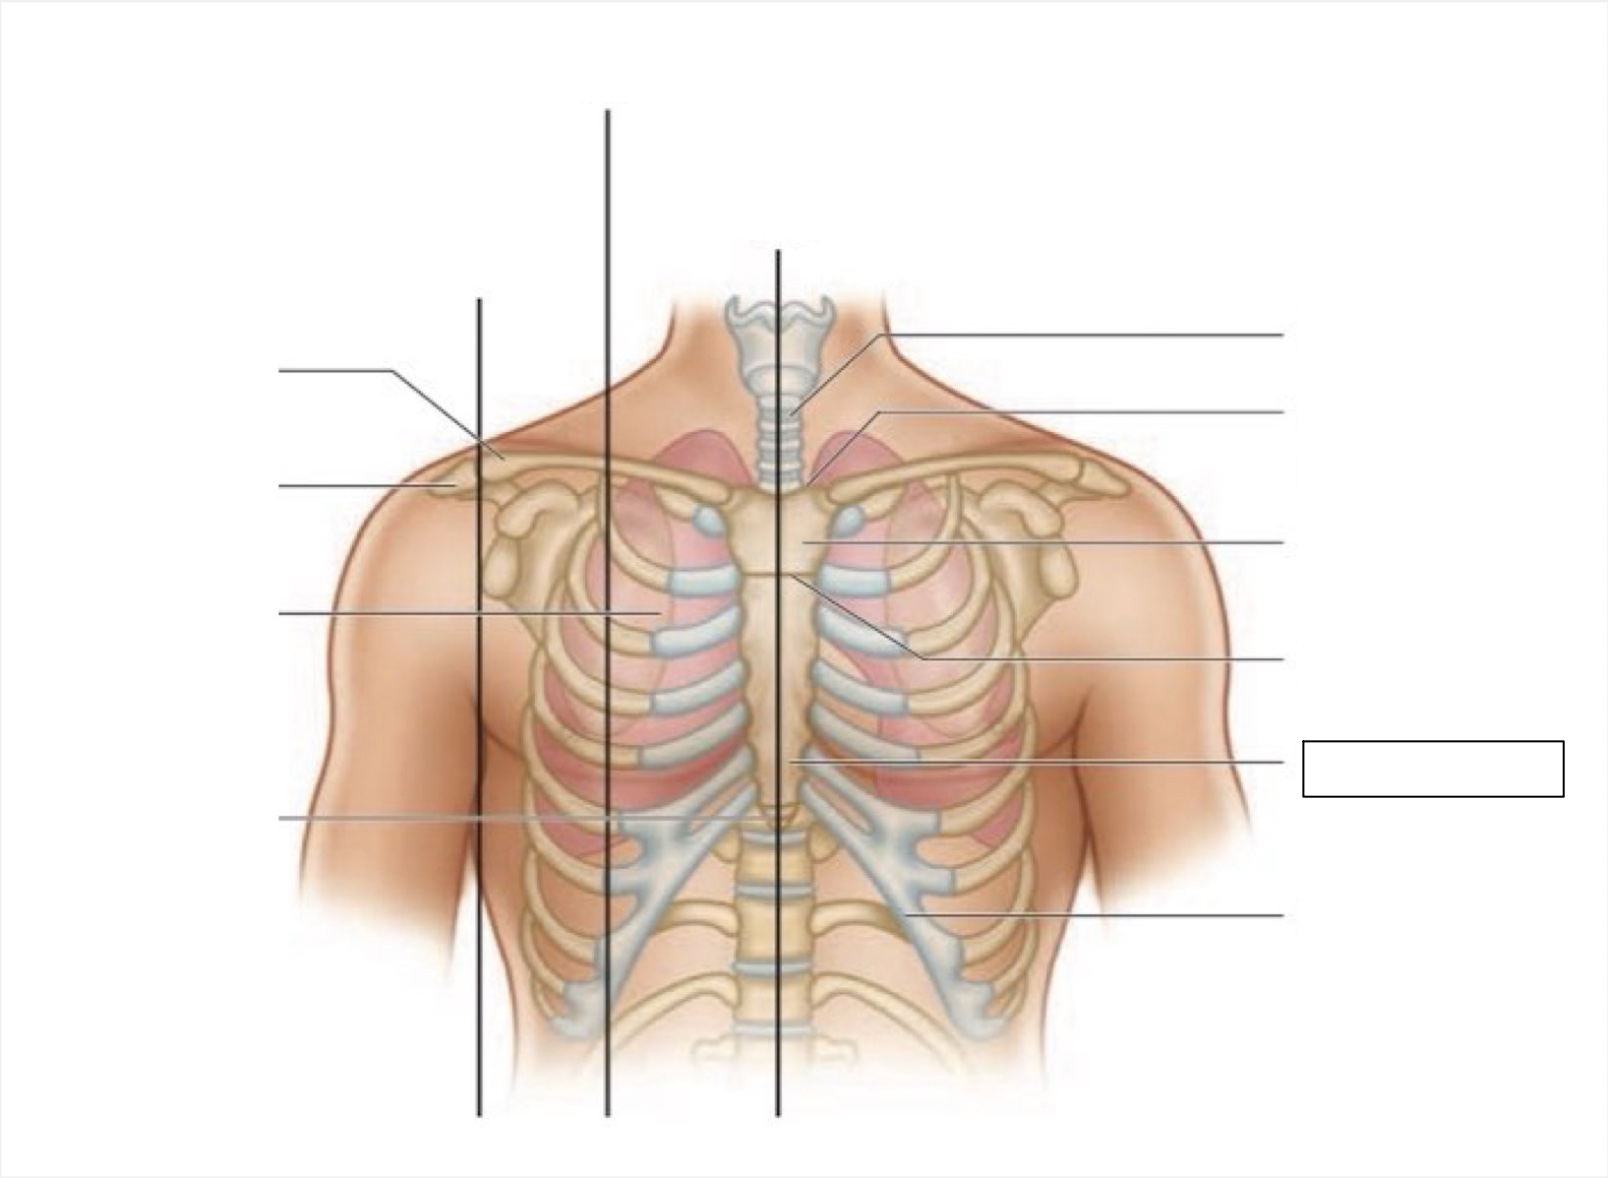

midsternal line

trachea

suprasternal notch

manubrium

angle of Louis

sternum

costal margin

xiphoid process

intercostal space

acromion

clavicle

anterior axillary line

midclavicular line